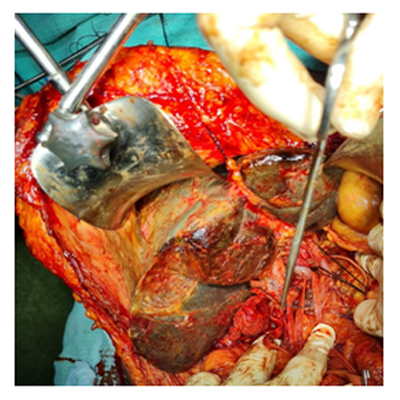

CAVITRON ULTRASONIC ASPIRATOR USED FOR LIVER RESECTION

LIVER RESECTION DONE USING CUSA

We have state of the art operating theatre with advanced surgical equipments. We have a Karl Storz Spies advanced HD laparoscopy operating system in addition to a 3 chip laparoscopy. We have installed advanced vessel sealing devices like Gen 11 harmonic scalpel, Ligasure from Valley Lab & Argon plasma coagulator. There is a recent addition of Cavitron Ultrasonic Aspirator (CUSA) system into our surgical armamentarium. We have the most recent powered Echelon endo-stapling devices. In addition to all these we have a constant supply of various types of advanced stapling devices for GI surgeries. Our endoscopy machines are having high definition with FICE Technology. Last but not the least we have semi flexible Ureteroscopy for managing common bile duct stones.